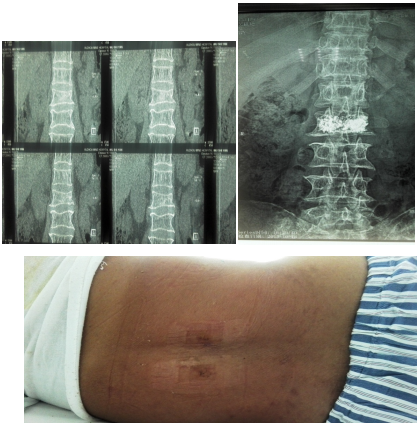

2.腰椎血管瘤部分患者没有临床症状不需要治疗,但也有一部分患者因血管瘤浸润造成背部酸胀疼痛、脊柱僵直、活动受限需治疗,大部分病人通过椎体成形微创手术可以消除症状。如血管瘤侵犯椎体周围软组织,压迫脊髓或马尾神经造成下肢疼痛无力,大小便障碍或截瘫症状者,则不单纯采用椎体成形术。近年来我科对单纯血管瘤行椎体成形术,取得了良好的效果。附典型案例如下: